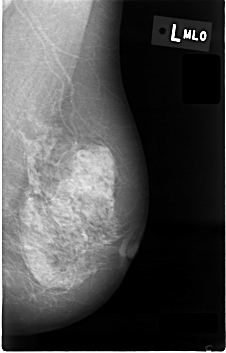

C_0004_1.LEFT_MLO

LEFT_MLO LINES 4584 PIXELS_PER_LINE 2936 BITS_PER_PIXEL 12 RESOLUTION 50 NON_OVERLAY